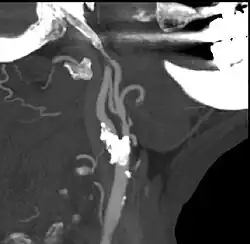

![]() Endarterectomía carotídea. | ||

La endarterectomía es un procedimiento quirúrgico para eliminar placas ateromatosas o bloqueos en el recubrimiento interior de una arteria obstruida por la acumulación de depósitos. Se lleva a cabo mediante la separación de la placa de la pared arterial, restableciendo de esta forma el flujo sanguíneo. Se aplica a diferentes arterias, con mucha frecuencia a la arteria carótida, denominándose en tal caso endarterectomía carotídea.

El procedimiento es ampliamente utilizado en la carótida del cuello cómo una manera de reducir el riesgo de accidente cerebrovascular, particularmente cuando la arteria carótica está estrechada en más del 70%. El procedimiento no está exento de efectos secundarios, uno de los más graves es provocar en un pequeño porcentaje de pacientes un accidente cerebrovascular en el momento de la operación.